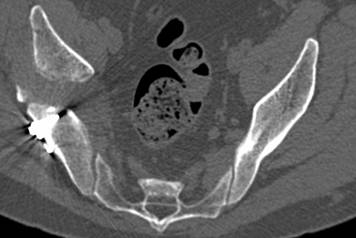

[Ortho] перелом правой половины таза

высылаю дополнительно  сканы.